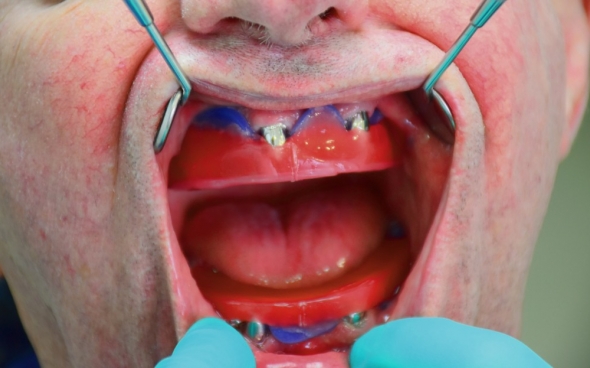

Metallkeramische Oberkiefer- und Unterkiefer-Vollbrücken

Der 48 jährige österreichische Patient erschien an unserer Zahnklinik zu einem Beratungstermin, wo eine Röntgenaufnahme und ein Kostenplan für metallkeramische Vollbrücken im Ober- und Unterkiefer mit insgesamt 25 Kronen erstellt wurden.